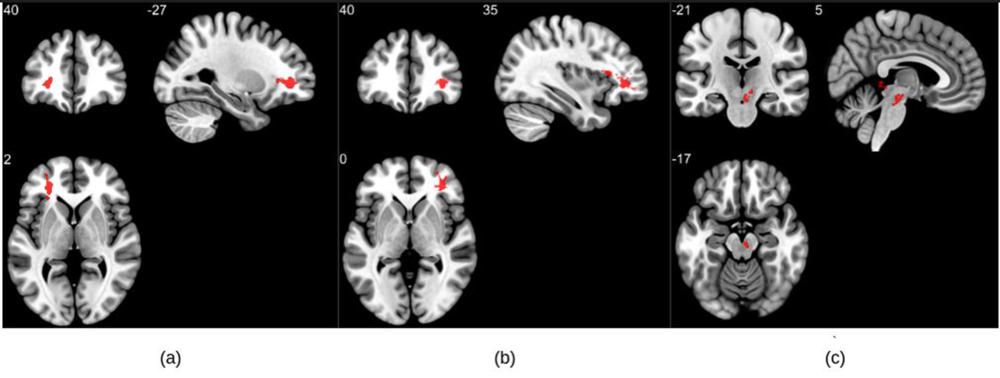

MRI results showed that patients who recovered from COVID-19 had significantly higher susceptibility values in the frontal lobe and brain stem compared to healthy controls. The clusters obtained in the frontal lobe primarily show differences in the white matter.

Portions of the left orbital-inferior frontal gyrus (a key region for language comprehension and production) and right orbital-inferior frontal gyrus (associated with various cognitive functions including attention, motor inhibition and imagery, as well as social cognitive processes) and the adjacent white matter areas made up the frontal lobe clusters.

The researchers also found a significant difference in the right ventral diencephalon region of the brain stem. This region is associated with many crucial bodily functions, including coordinating with the endocrine system to release hormones, relaying sensory and motor signals to the cerebral cortex and regulating circadian rhythms (the sleep-wake cycle).

Figure 1. Group analysis on susceptibility-weighted imaging exhibiting higher susceptibility-weighted imaging values in the COVID group when compared to healthy controls. Three significant clusters were found primarily in the white matter regions of the pre-frontal cortex and in the brainstem. The clusters (a) and (b) are observed bilaterally in the cerebral white matter near the orbitofrontal gyrus, whereas (c) lies in the midbrain region.